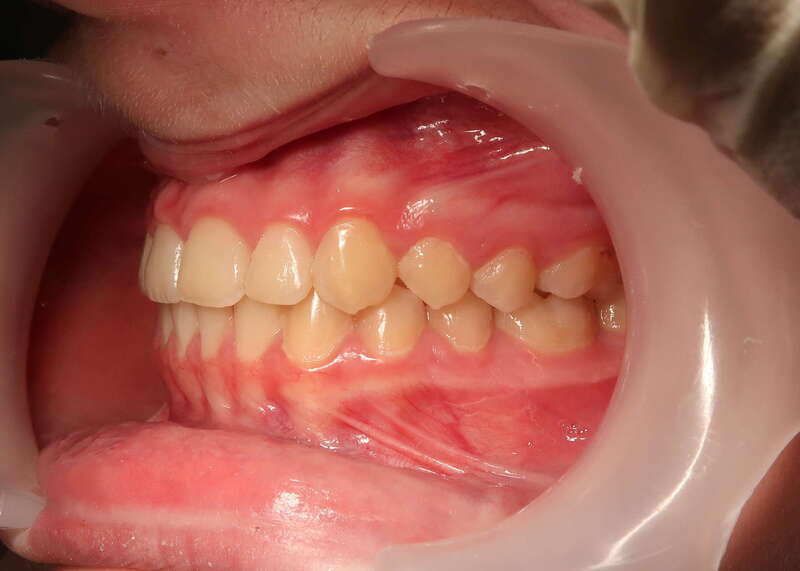

Cas n°1 traité par aligneurs - adolescent

Ce cas d’une adolescente illustre la correction d'une Classe II avec supraclusion par aligneurs. La stratégie thérapeutique a reposé sur une distalisation séquentielle de l'arcade supérieure. Ce mouvement précis a permis de reculer les dents maxillaires étape par étape pour annuler le surplomb (overjet) sans extractions.

Résultats clés :

• Correction fonctionnelle : Retour à un engrènement de Classe I stable et correction du recouvrement vertical.

• Esthétique restaurée : Harmonisation globale du sourire et du profil.

• Approche moderne : Un traitement discret, confortable et hautement prévisible.

Le résultat final montre une occlusion saine et un sourire parfaitement aligné, garantissant une santé dentaire et articulaire optimale pour l'avenir.